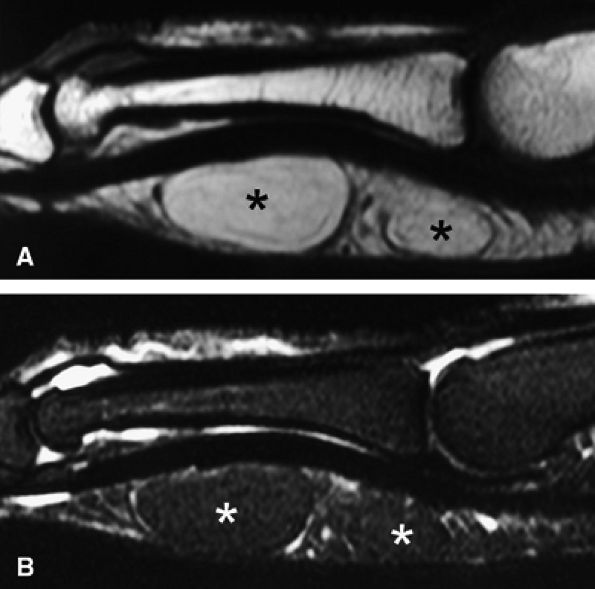

FIGURE 11.83 ● Lipoma. Sagittal T1-weighted image (A) and STIR image (B) depicting a bilobed lipoma (asterisks) of the palmar aspect of the proximal phalanx. The lesion demonstrates high signal on the T1-weighted image and low signal on the STIR image, similar to subcutaneous fatty tissue.

|